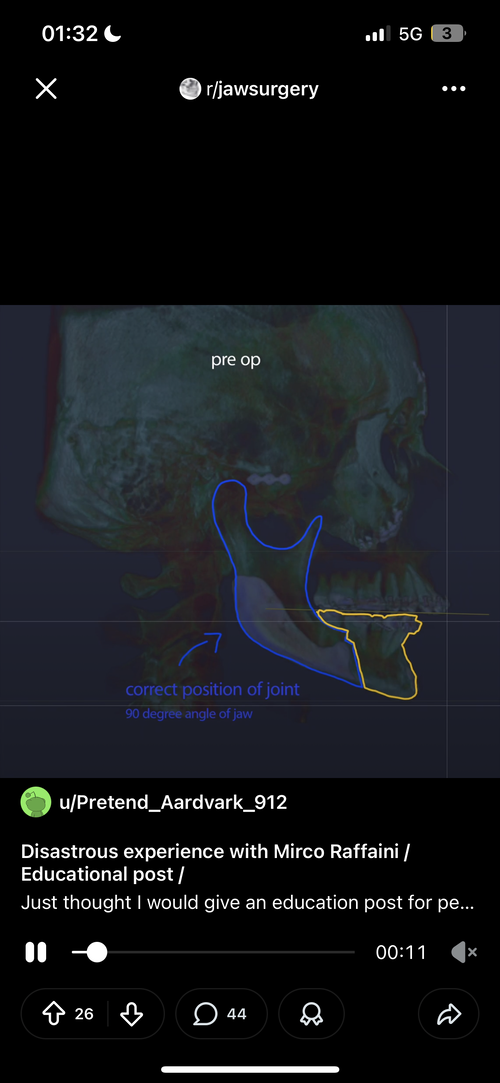

He rotated my proximal segment assymetrical.

The genioglossus are attached to the mandible, rotating the proximal segment assymetrical=assymetrical tongue.

He rotated my proximal segment assymetrical.

The genioglossus are attached to the mandible, rotating the proximal segment assymetrical=assymetrical tongue.

My reality is this now: Doing a revision as to where I tell my surgeon to do reorientation of my proximal segment to make the tongue pararell and also FUCKING advance it the same amount Ramieri chose to do set back.